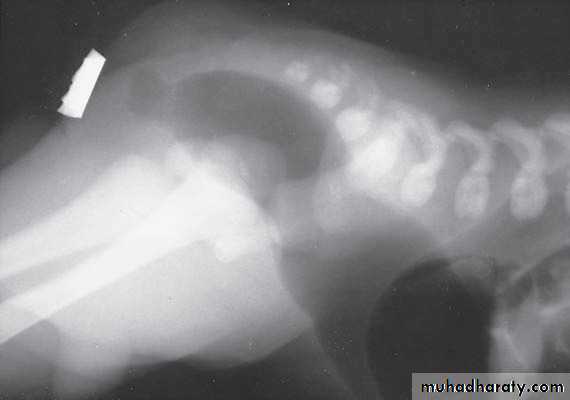

2-Lateral invertogram ( pubococcegeal line) 18-24hr.after birth.

-gas shadow above this line suggest high type.

- gas shadow below suggest low type.

3-lateral decubitus X-ray.